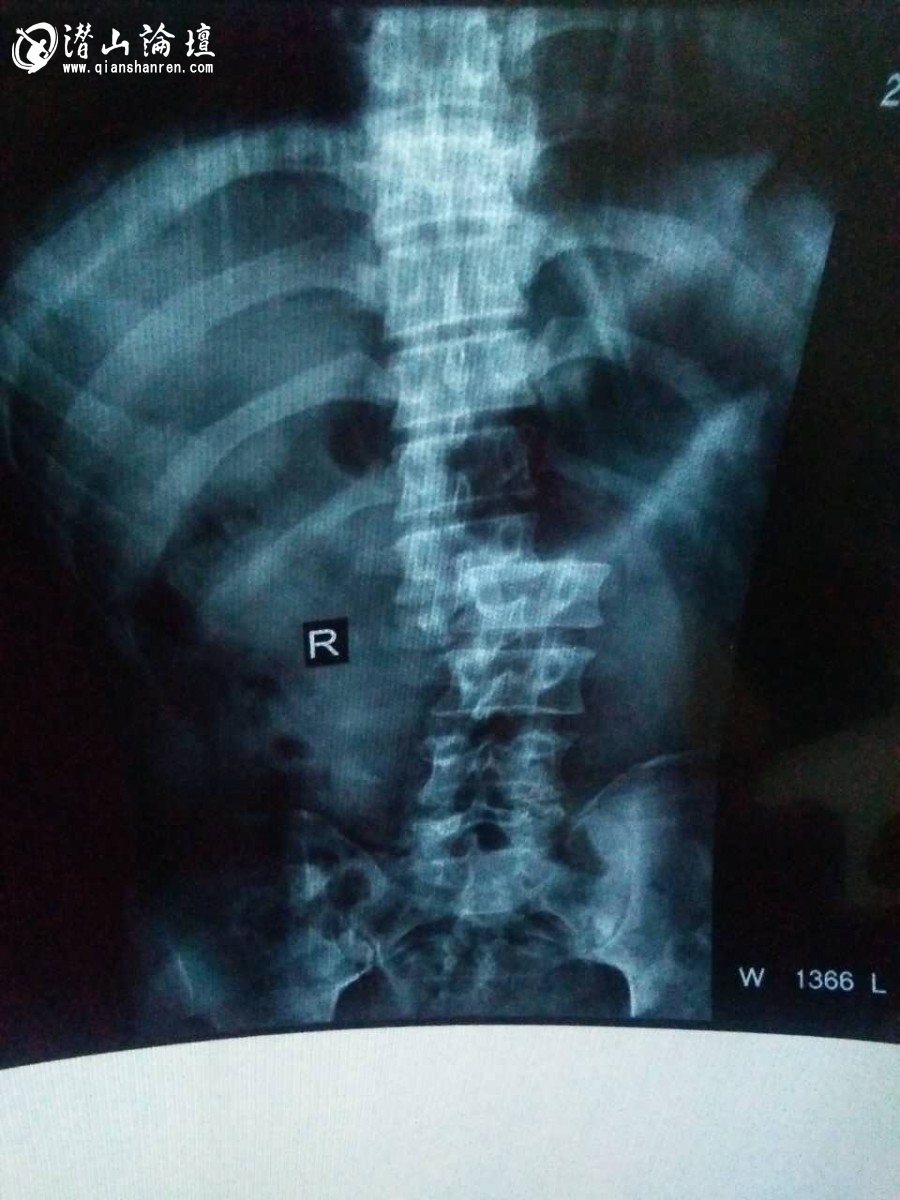

我的父亲钱伲松,在本月10日,为当地的一农户人家盖房子时,不幸从3层楼高的搭建物上摔下来,送到县医院和市医院都被拒收,被迫转到了合肥市安医二附院,医院确诊父亲的病情为腰脊椎断裂,内脏损伤,医生说父亲病情很重,需在重症监护室观察,诊治以后最理想的状态也是个卧床不起的瘫痪人。我的父亲才41岁啊,一眨眼变成了这样,为什么在一个人如此重要的时刻上天会有这么一个安排,要让他从此不能再行走,下辈子都要卧床不起?妹妹还在上初中,爷爷今年也76岁了,家里几乎陷入了绝望。但不管怎样我们都要为父亲治,哪怕是只有一点点好转机会。因为她是母亲的好丈夫,是我的好父亲,更是爷爷的好儿子啊,只要他不离开我们,即使他真的要躺在床上一辈子,我们就会觉得很踏实,我们都要好好陪伴着他!

小学毕业后,父亲没有再上学,在家里干了几年农活,后来就拉扯着跟附近村子一个师傅学瓦匠手艺。三年学徒时间,父亲吃了很多苦,起早贪黑,重活累活不含糊,正因为如此,父亲身体透支严重,通常的腰腿疼不说,严重时甚至吐了几次血,直到现在父亲已经身患腰间盘突出症多年,但这些我的父亲都是噎着扛着。